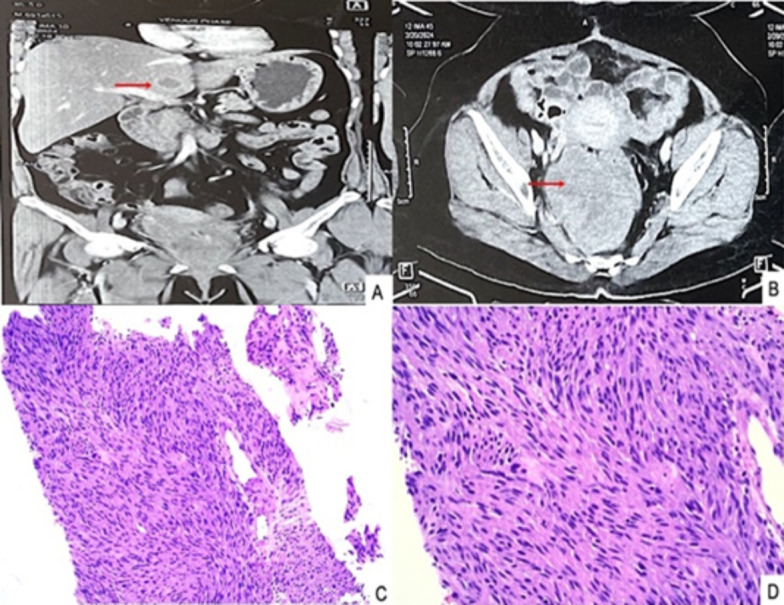

Gastrointestinal stromal tumours (GIST) are rare mesenchymal tumours which represent 1% to 3% of all gastrointestinal neoplasms. Rectal location of GIST is extremely rare accounting for 5% of GIST and only 0.1% of rectal tumours. They usually metastasise to the liver (65%). We hereby report a case of rectal stromal tumour with hepatic metastasis. A 55-year-old female presented with pelvic pain, associated with rectal bleeding. A thoracoabdominal computed tomography showed a large heterogeneous enhancing mass, arising from the rectum, anal canal and distal sigmoid colon measuring 12.3x8.7x7.6cm. Based on histopathological examination followed by immunohistochemistry, she was diagnosed with locally advanced rectal GIST. The tumour reduced in size after neoadjuvant-targeted treatment with imatinib. A local resection of the rectal GIST was successfully performed, and a diversion colostomy was done, later colostomy bag was attached. Following the operation, oral imatinib treatment was continued. On subsequent follow-up, her triple phase CECT whole abdomen showed multiple small well-defined peripherally enhancing hypodense liver lesions, the largest measuring 29x18mm suggestive of metastases. Ultrasound-guided fine needle aspiration from a liver lesion was reported as metastatic GIST. The patient underwent surgery, sunitinib was started and was discharged in stable condition. Thus, cytologic examination provides rapid interpretation, is a less invasive technique than open biopsy, and provides a cost-effective modality for diagnosing and managing inaccessible lesions.